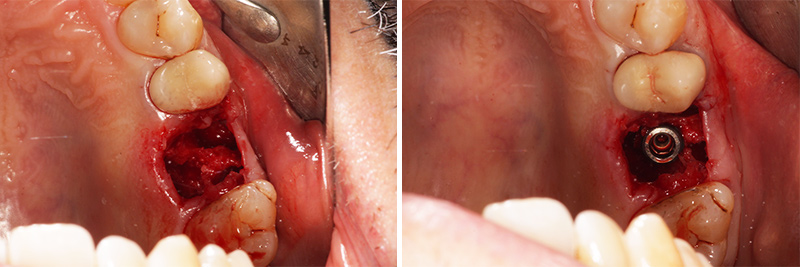

Fig. 01 : ablation de la couronne et de l’inlay-core.

Fig. 01 : ablation de la couronne et de l’inlay-core.

Fig. 02 : extraction et curetage de l’alvéole, désinfection bétadine H2O2 et pose d’un implant 4,5 x 10 mm (Megagen).

Fig. 02 : extraction et curetage de l’alvéole, désinfection bétadine H2O2 et pose d’un implant 4,5 x 10 mm (Megagen).